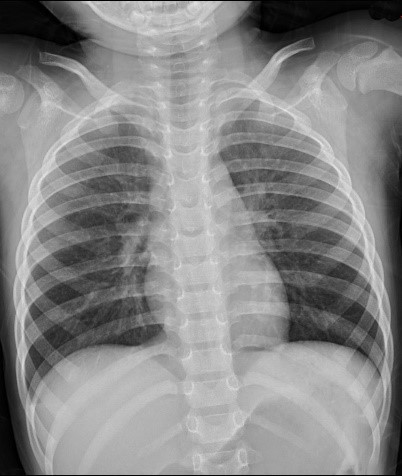

实体滤线栅

|

通过以上病例可以看出同一个病人,分别在不使用滤线栅,使用实体滤线栅,和使用虚拟滤线栅之后图像,可以看到右边两幅图像的对比度较左边图像明显提高。而且国内临床数据显示肥胖患者明显优于正常体型和偏瘦体型。